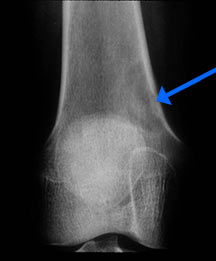

- Radiographically variable appearance: may appear benign (geographic) or malignant (permeative or moth eaten)

Radiographic Presentation